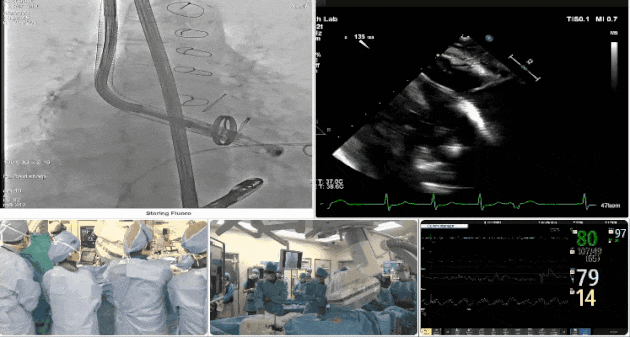

第三例患者手術難點

1、心率慢(<50bpm),術后起搏器植入風險,術前需評估心電圖情況;2、CT顯示主動脈瓣機械瓣置換術后,需明確三尖瓣是否同期做過修復。

術中TEE觀察夾持件的位置

術后DSA

術后超聲評估瓣膜穩定性良好,無瓣周漏

手術過程